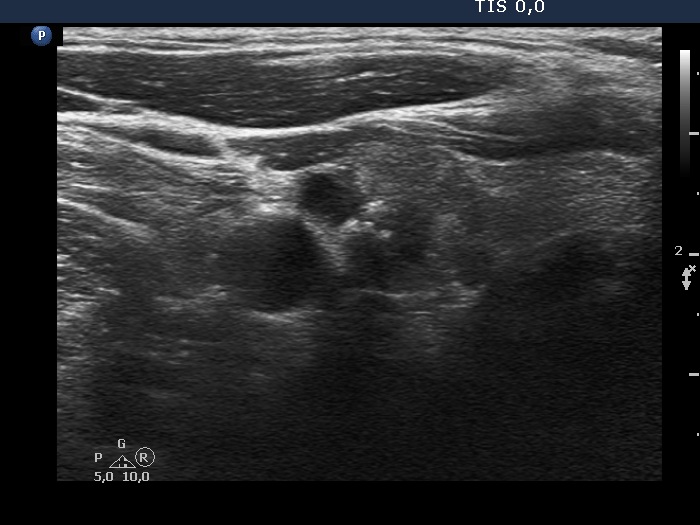

Right lobe, another transverse view. The nodule has microcalcifications.